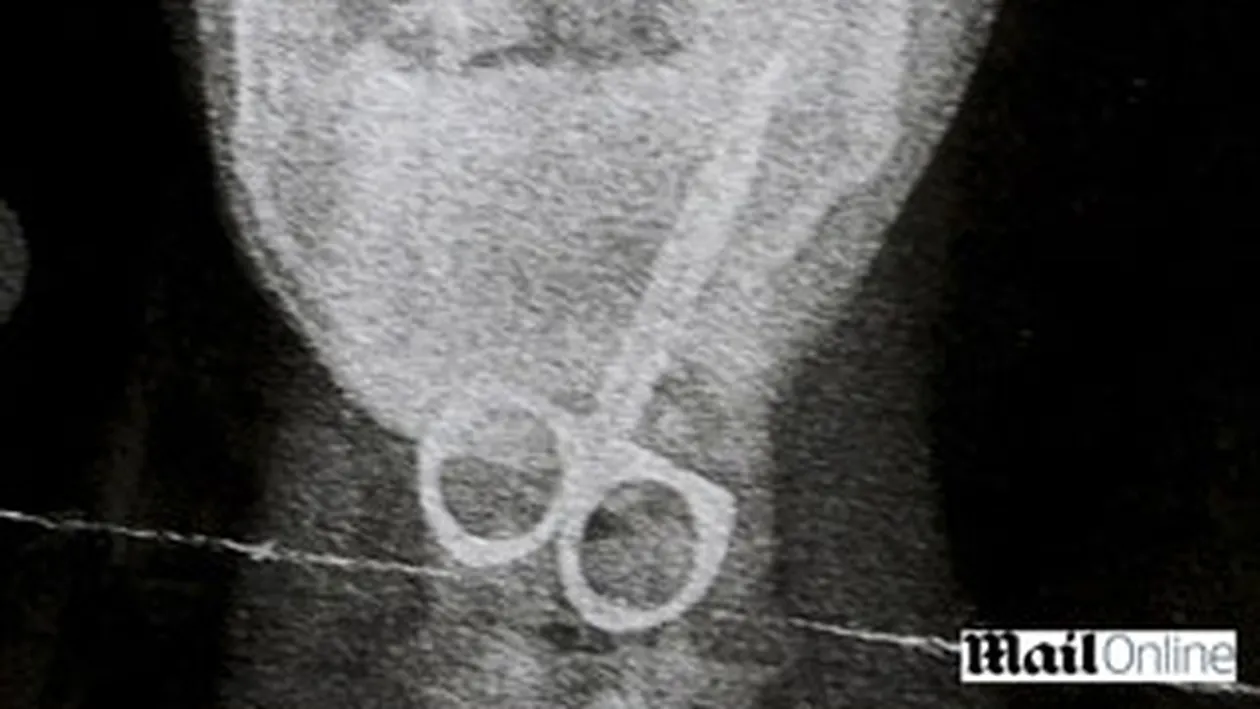

Un baietel de 12 ani din Marea Britanie a ajuns la spital cu un foarfece in gat, pe care doar ce-l inghitise. Copilul are dificultati de invatare si nu constientizeaza pericolul.

Cea care a descoprit ce patise baietelul este chiar mama lui care a observat ca micutul scuipa sange in timp ce tusesee. Femeia l-a dus de urgenta la spital unde medicii au fost socati de ceea ce au vazut pe radiografie.Doctorii au reusit sa inlature obiectul din gatul baiatului sub anestezie generala. Ei au declarat ca a avut mare noroc ca foarfecele nu i-a cauzat rani majore.”Intr-o prima etapa nu am realizat cat de grava era situatia. Credeam ca a inghitit un capac de pix sau ceva similar. Abia cand Curtis a inceput sa tuseasca si sa scuipe sange mi-am dat seama ca se intamplase ceva groaznic”, si-a amintit Karon, mama baietelului. „Ziua in care Curtis a facut boroboata asta a fost cea mai cumplita din viata mea. Din fericire, nu a patit nimic. De regula, sunt atenta cu fiul meu, dar, fiind in crestere si plin de energie, imi este din ce in ce mai greu”, a adaugat femeia.